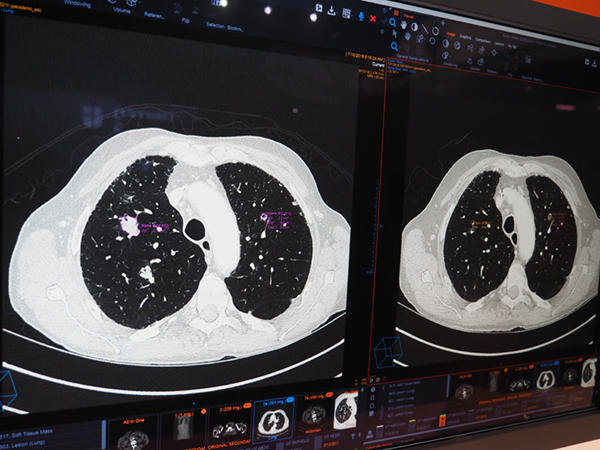

3) CTにおけるLung nodule(肺結節)の自動抽出

胸部CT画像で肺結節を自動で認識し抽出。計測結果はレポートに自動で反映される。従来のビューワでは,結節の選択や計測はセミオートで読影時に選択する必要があったが,AIの自動認識技術で自動化し,計測も自動で行われる。読影医は選択された結節の採否を判断するだけでよく,診断業務をサポートできる。

CTにおける自動でのLung nodule(肺結節)の自動抽出(W.I.P.)